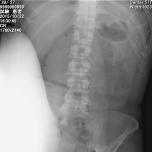

こちらのレントゲンは、膝を身体の真正面方向に向かって動かしたときの最高点を撮影した画像です。膝のいちばん上は11番目の胸椎と12番目の胸椎の間くらいの高さでした。